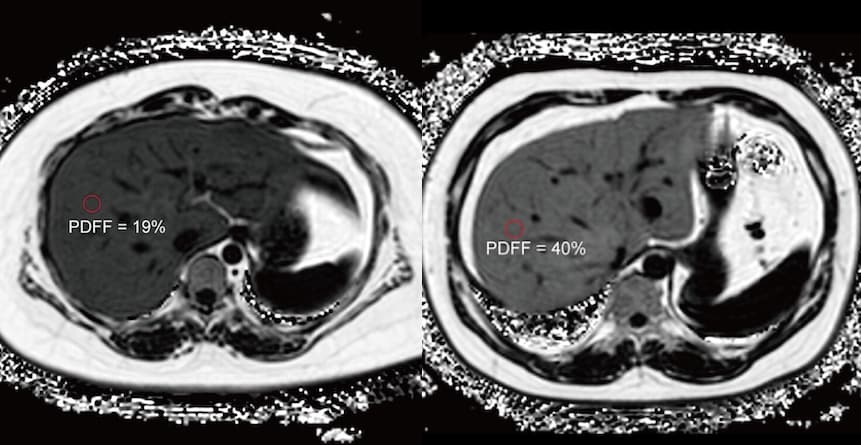

La fraction de densité de proton par IRM est reconnue comme un outil d’évaluation de référence pour quantifier la graisse hépatique. Un travail de recherche publié dans la Revue Radiology évalue la gravité de la stéatose aux moyens de cette pratique. Cet outil IRM est validé par les chercheurs pour...